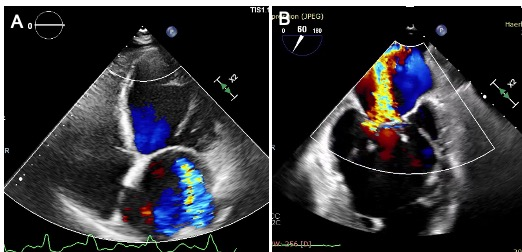

术前经胸和食道超声结果。左图:经胸超声提示心房心室扩大,二尖瓣重度反流;右图:食道超声提示二尖瓣重度反流(彩色血流)。